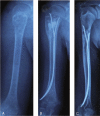

Unicameral bone cyst (UBC) is a benign fluid-filled lesion, mainly located in the metaphyses of long bones in children and adolescents. Elastic stable intramedullary nail (ESIN) is adopted in our institute for UBCs since 2010, and bone grafting was performed simultaneously. This study aims to evaluate the efficacy of ESIN decompression combined with different bone graft materials.All patients with the diagnoses of UBCs of the humerus, treated with ESINs and bone grafting between January 2010 and June 2018, were analyzed retrospectively. The bone grafting included injectable calcium sulfate, a mixture of the autologous iliac bone and allogeneic bone. All patients were categorized into 2 groups: ICS (injectable calcium sulfate) group and MIX (a mixture of the autologous iliac bone and allogeneic bone, ratio: 1:3) group. All the information was collected from the Hospital Database.In all, 17 patients (8.8 ± 2.3-year-old, male 8, female 9) in the ICS group and 19 patients (8.9 ± 1.9-year-old, male 10, female 9) in the MIX group were included in this study. Patients in both groups were followed up for more than 2 years (average, 3.4 ± 1.3 years). No recurrence was observed in either group. There was no significant difference between the two groups concerning the patient's demographic parameters, including sex, age, and affected side. All patients in both groups displayed excellent and good shoulder function, and there was no significant difference between the 2 groups (P = .29). As for the Capanna classification, there was no significant difference between these 2 groups (P = .78).Intramedullary nailing has the advantage of a minimally invasive procedure, immediate stability, and continuous decompression. ICS showed similar results as a mixture of the autologous iliac bone and allogeneic bone.